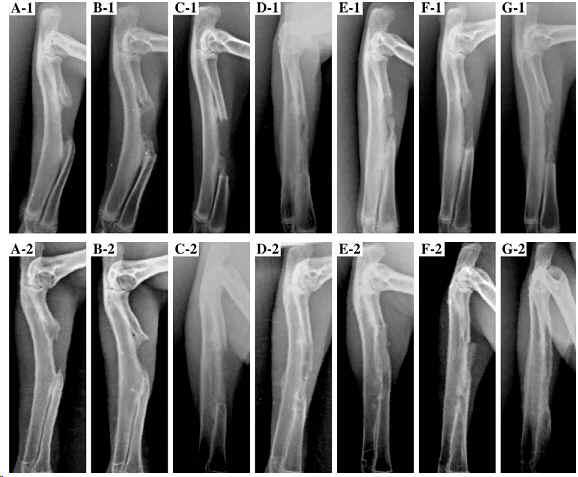

[Abstract]: Nanohydroxyapatite (op-HA) surface-modified with l-lactic acid oligomer (LAc oligomer) was prepared by LAc oligomer grafted onto the hydroxyapatite (HA) surface. The nanocomposite of op-HA/PLGA with different op-HA contents of 5, 10, 20 and 40wt.% in the composite was fabricated into three-dimensional scaffolds by the melt-molding and particulate leaching methods. PLGA and the nanocomposite of HA/PLGA with 10wt.% of ungrafted hydroxyapatite were used as the controls. The scaffolds were highly porous with evenly distributed and interconnected pore structures, and the porosity wasaround 90%. Besides the macropores of 100-300microm created by the leaching of NaCl particles, the micropores (1-50microm) in the pore walls increased with increasing content of op-HA in the composites of op-HA/PLGA. The op-HA particles could disperse more uniformly than those of pure HA in PLGA matrix. The 20wt.% op-HA/PLGA sample exhibited the maximum mechanical strength, including bending strength (4.14MPa) and compressive strength (2.31MPa). The cell viability and the areas of the attached osteoblasts on the films of 10wt.% op-HA/PLGA and 20wt.% op-HA/PLGA were evidently higher than those on the other composites. For the animal test, there was rapid healing in the defects treated with 10 and 20wt.% op-HA/PLGA, where bridging by a large bony callus was observed at 24weeks post-surgery. There was non-union of radius defects implanted with PLGA and in the untreated group. This was verified by the Masson''''''''s trichrome staining photomicrographs of histological analysis. All the data extrapolated that the composite with 10 and 20wt.% op-HA exhibited better comprehensive properties and were the optimal composites for bone repairing.